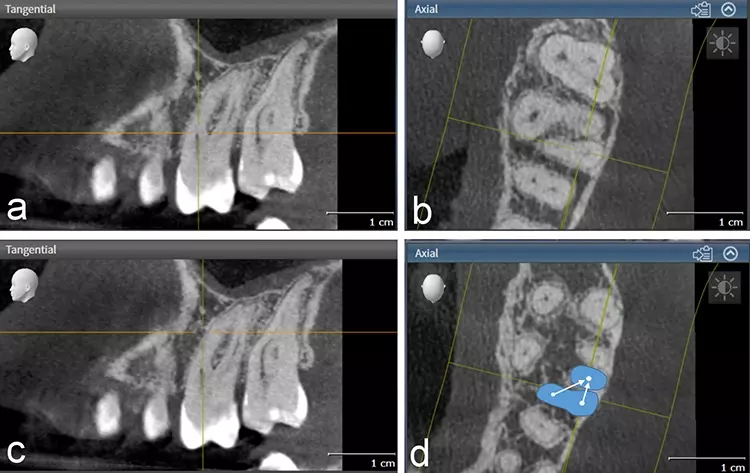

Da die zweidimensionale Diagnostik aufgrund der Länge der Wurzeln erschwert war und sich zudem eine komplexe Anatomie vermuten ließ (Abb. 1), wurde zur erweiterten Diagnostik und zur Behandlungsplanung ein kleinvolumiges DVT angefertigt (Orthophos SL, Dentsply Sirona, Volumen Ø 5 x 5 cm, Auflösung 80 μm). In der DVT-Aufnahme zeigte sich eine apikale Osteolyse an der palatinalen Wurzelspitze mit reaktiver Schwellung der angrenzenden basalen Kieferhöhlenschleimhaut (Abb. 2). Der periapikale Knochen an den vestibulären Wurzeln stellte sich unauffällig dar.

Eine apikale Fusion der Wurzeln mit zusätzlicher Konfluation des mesio-bukkalen und des disto-bukkalen Kanals wie bei Zahn 27 lag an dem zu behandelnden Zahn nicht vor. Die Wurzelkanalmorphologie (Krümmung, Konfluation) der mesiobukkalen Wurzelkanäle von Zahn 26 ließ sich gut anhand verschiedener axialer Ebenen (Abb. 3) erkennen und mit Hilfe einer Planungssoftware (SICAT Endo, SICAT) dreidimensional visualisieren (Abb. 4). Da in diesem Fall der zweite mesio-bukkale Kanal eine Krümmung sowohl in distaler Richtung als auch nach vestibulär aufwies, wurde vorab geplant, den Kanal lediglich bis zur Konfluation mechanisch zu erweitern.